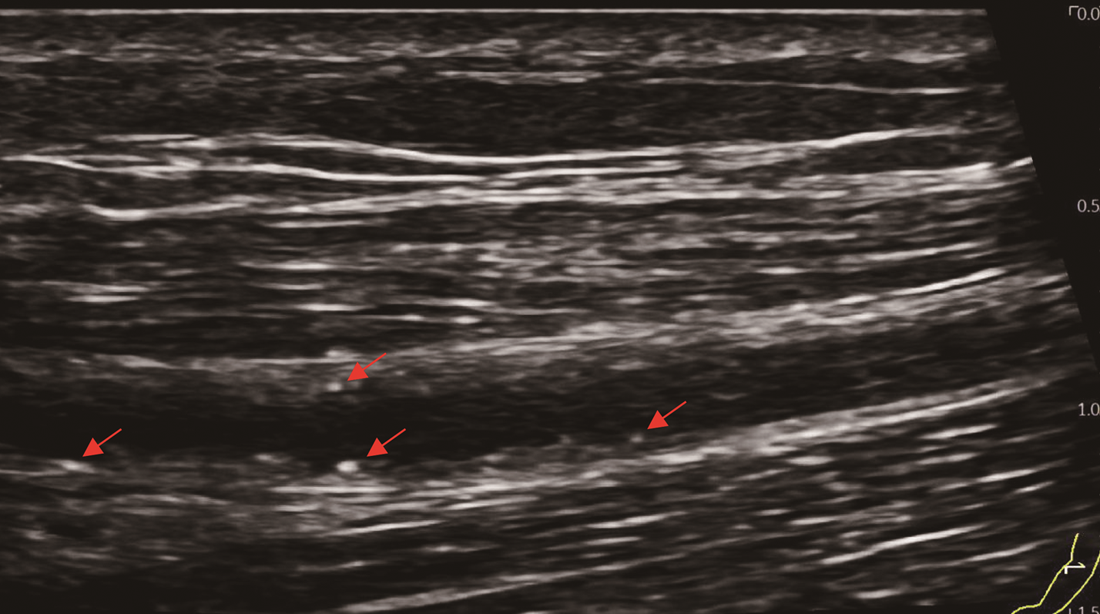

辅助检查:心电图检查示窦性心律,室性早搏。血管彩超见右上肢动脉中内膜点状钙化斑形成,左上肢动静脉内瘘血管中内膜点状钙化斑形成(图1)。双下肢和双手X线检查:双手诸骨骨质密度不均匀增高,部分远节指骨骨质吸收(图2),右手指骨周围见血管钙化影和结节状高密度影,诸小关节在位,关节间隙尚可,周围软组织未见明显肿胀;双髋关节在位,髋关节间隙变窄,双侧股骨骨质密度增高。双膝、双踝关节,双足诸小关节在位,关节间隙尚可,双膝、双踝、双足关节面下骨质密度不均匀增高(图2)。心脏彩超检查:双心房扩大,二尖瓣环钙化,二尖瓣轻度反流,三尖瓣轻-中度反流和卵圆孔未闭(房水平左向右分流)。胸腹部计算机体层成像(CT)平扫:(1)双肾萎缩钙化;(2)全身广泛骨质密度增高;(3)脾脏饱满,动脉粥样硬化。与2021年5月21日胸部X线片比较,胸廓诸骨骨质密度增高稍有进展(图3)。骨髓涂片检查:骨髓细胞增生减低,中性粒细胞系占68.0%,以分叶核细胞为主,嗜酸细胞可见;红细胞系占1.2%,成熟红细胞大小不均,部分细胞中心淡染区扩大;淋巴细胞比例增高;未见巨核细胞,血小板散在。骨髓病理检查结果:骨髓部分组织破碎,伴纤维组织增生,增生程度无法明确判断,骨髓小梁结构紊乱伴髓腔变形,部分小梁硬化,髓腔内见多量结晶样物沉积,有少量偏成熟粒细胞散在分布,未见红系和巨核系(图4A),偏振光镜下可见特征性双折射(图4B)。

本例PH患者接受维持性血液透析治疗4年,除肾脏受累外,还伴有多系统病变,总结如下。(1)重度顽固性贫血:患者乏力明显,精神萎靡,贫血貌,在外院反复接受输血治疗,且在使用较大剂量罗沙司他情况下,血红蛋白仍波动在65 g/L左右。患者粪便潜血阴性,可排除消化道出血,结合病史、骨髓活检以及硫代硫酸钠经验性治疗效果,证实草酸盐结晶骨髓沉积是骨髓造血受损的主要病因。既往也有文献报道重度顽固性贫血是PH患者特征性表现之一。需要注意的是,本例患者以贫血为主要表现,白细胞和血小板计数正常,这与既往报道的全血细胞减少存在差异[5, 6]。经文献检索发现,本例患者骨髓组织草酸盐结晶的病理表现是目前已报道病例中最具有特征性改变的病例。(2)骨痛、骨关节畸形和骨质密度增高:患者主诉双手疼痛麻木,伴有双足跟疼痛,四肢关节活动受限。结合其胸腹部CT表现为全身广泛骨质密度增高,以及X线检查示双手诸骨骨质密度不均匀增高,部分远节指骨骨质吸收;髋关节间隙变窄;双侧股骨骨质密度增高;双膝、双踝、双足关节面下骨质密度不均匀增高,提示草酸盐沉积于骨导致骨钙化,而非一般性肾性骨病,后者常以骨质疏松、骨软化、纤维囊性骨炎及病理性骨折为特征。由于PH的罕见性和缺乏大样本的系统研究,PH骨损害的流行病学特征目前仍不清楚。值得注意的是,即使在未出现临床症状时,部分患者已出现明显骨损害影像学改变[7]。我们既往报告的1例PH 1型患者也是以骨质密度增高、骨组织破坏、骨结构紊乱,草酸钙沉积骨及骨周组织改变为临床特征[3],与本例相似。因此,早期的骨骼系统筛查可能对PH诊疗有着重要价值。(3)心脏病变:虽然目前尚无草酸盐沉积于心脏的直接证据,但本例患者血压较前显著降低,波动在80~83/54~50 mmHg,肌钙蛋白I升高;心脏彩超检查示双心房扩大、二尖瓣环钙化。心脏病变受到多种因素的影响,本例患者除考虑贫血外,还可能与草酸盐沉积于心脏组织有关。既往也有草酸盐沉积于心脏组织的文献报道[8]。(4)血管钙化:草酸盐沉积于血管是PH患者发生血管钙化的重要发病机制[9]。本例患者血管彩超结果示左右上肢动脉中内膜点状钙化斑形成;胸腹部CT亦可见较广泛血管钙化;X线检查示右手指骨周围见血管钙化影。目前,草酸盐沉积于血管的选择性仍不明确。研究显示,皮肤微血管功能障碍可作为PH 1型患者心血管损害的早期标志物[10],提示草酸盐较易沉积于微小血管。(5)低白蛋白血症:本例患者体重指数、血脂正常,透析充分性良好,自诉饮食合理,每次透析使用人血白蛋白10 g,但仍表现为顽固性低白蛋白血症,这与既往文献报道并不完全一致[11, 12],且与PH分型无关[13]。目前,PH患者发生低白蛋白血症的病因不清楚,考虑到PH是以肝脏特异性基因突变导致草酸盐产生过多为临床特征,肝脏基因突变间接引起的肝脏白蛋白合成异常可能是顽固性低白蛋白血症的原因。(6)高凝状态:本例患者平素使用大剂量抗凝药物。即使在高强度抗凝情况下,透析器中仍可见血栓形成。同时,近6个月来反复因动静脉内瘘血栓形成而导致动静脉内瘘功能不良,血D-二聚体多次较正常值升高10多倍,纤维蛋白(原)降解产物升高数倍,表明本例患者存在高凝状态和纤溶亢进。经文献检索发现,本例为PH合并高凝状态的首次报道,其发生机制仍不清楚,推测可能与转氨酶相关基因突变导致凝血因子和纤溶蛋白合成异常及草酸盐沉积引起内皮损伤有关[14]。既往有个案报道显示,肝移植能够治愈合并血栓形成倾向的PH 1型患者[15]。